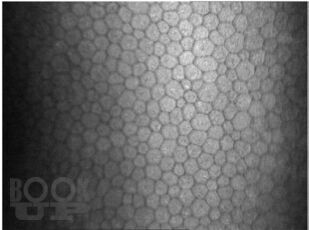

Воспалительные заболевания роговицы

В учебном пособии подробно изложены анатомотопографические особенности строения, кровоснабжения и иннервации роговой оболочки. Детально описанаклиническая картина воспалительных заболеваний роговицы экзо- и эндогенного происхождения. Изложены современные принципы консервативного и хирургического лечения патологии роговицы воспалительного генеза.